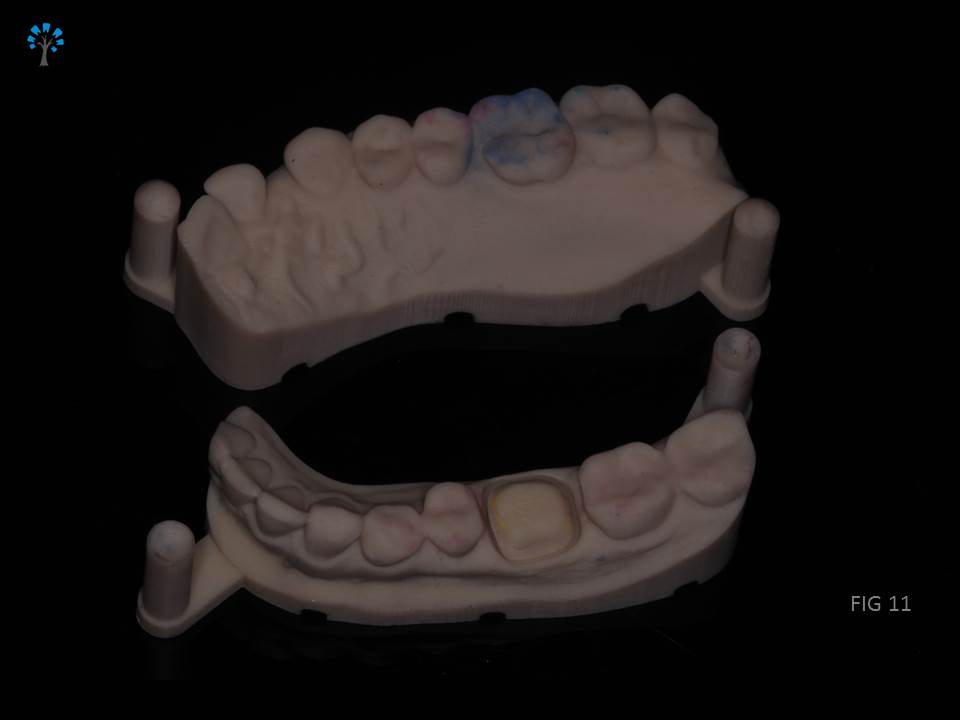

Crown Preparation was done and a digital scan (fig 11) for an impression was obtained.